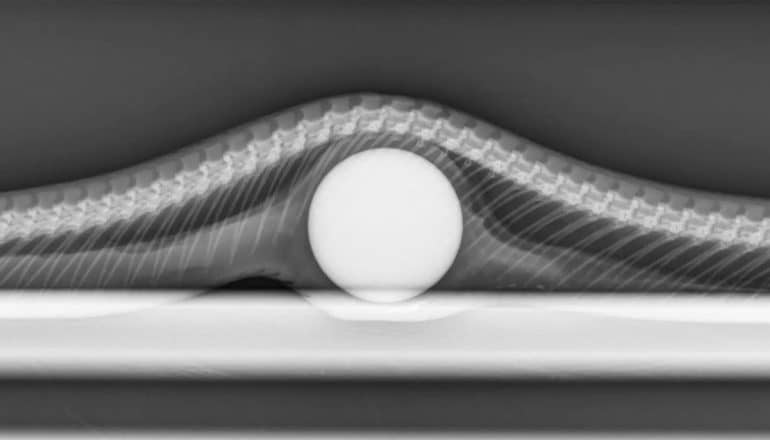

x-ray image of ball in snake

When a hungry snake eats a golf ball instead of an egg, it can cause serious problems.